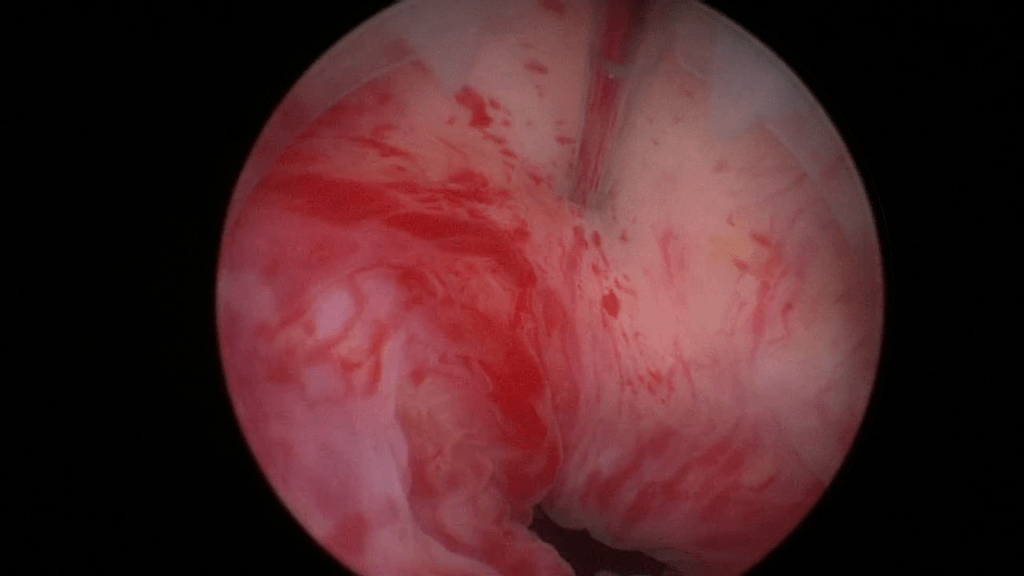

Beginn with a thorough cystoscopy. Patients that have incontinence recurrence should be examined for sling or even suture erosion. Watch out for tumors or stones.

The bladder neck.